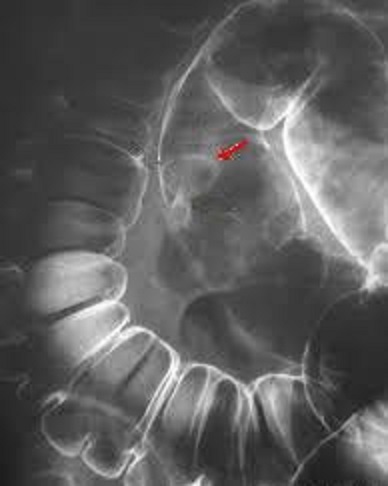

Image radiologique d'une

polyp du colon sigmoide . Ápect en forme de champignon

du polyp situe au face anterieur du colon avec

pedicule ( fleche rouge ) . Image de lavement du

colon en double de contrast . |